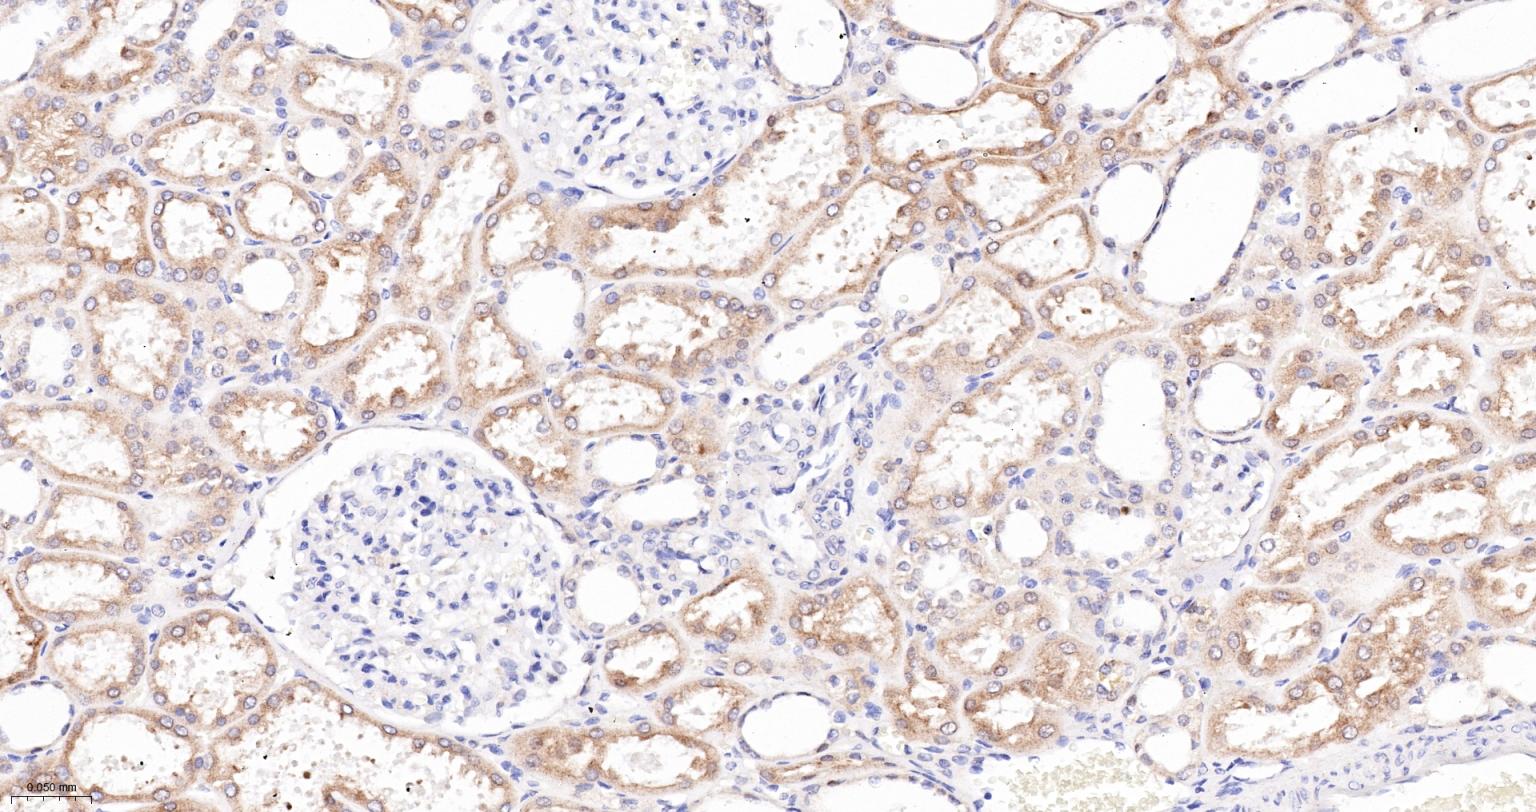

Paraformaldehyde-fixed, paraffin embedded Human Kidney; Antigen retrieval by boiling in sodium citrate buffer (pH6.0) for 15 min; The section was incubated with CYPOR Monoclonal Antibody, Unconjugated (bsm-61747R) at 1:200 overnight at 4°C, followed by conjugation to the bs-0295G-HRP and DAB (C-0010) staining.